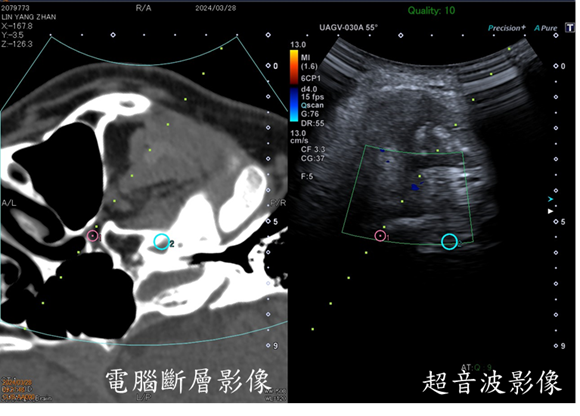

隨著超音波儀器日新月異,在中高階的超音波儀器搭載電腦斷層融合軟體已經變成一種趨勢。我們簡單地來描述一下這是怎麼做到的,首先,先在病人頭上黏貼磁導裝置,然後針對顱底神經孔做電腦斷層的掃描。接下來,我們將顱底電腦斷層的影像傳送到超音波機器中,再把超音波的探頭擺到病患的臉上,這時只要簡單地按下同步鍵,我們可以看到超音波的螢幕上出現電腦斷層的影像(圖1)。當我們隨意地挪動超音波探頭,電腦斷層影像就會與超音波影像『同步性』地變化。

一般來說,超音波最讓人詬病的是要熟練的操作儀器有一定的難度,尤其是顱底超音波。由於臉骨的遮擋,使得顱底神經孔的超音波定位尤其困難。有了上述融合電腦斷層影像的即時性超音波後,我們就能在超音波螢幕中標註電腦斷層影像上想要放置針尖的神經孔洞,此時,與之同步的超音波影像也會同時出現標註點(圖1)。此時我們只要將針尖刺入標註點,就可以完成治療中最重要的『精準影像導引技術』。